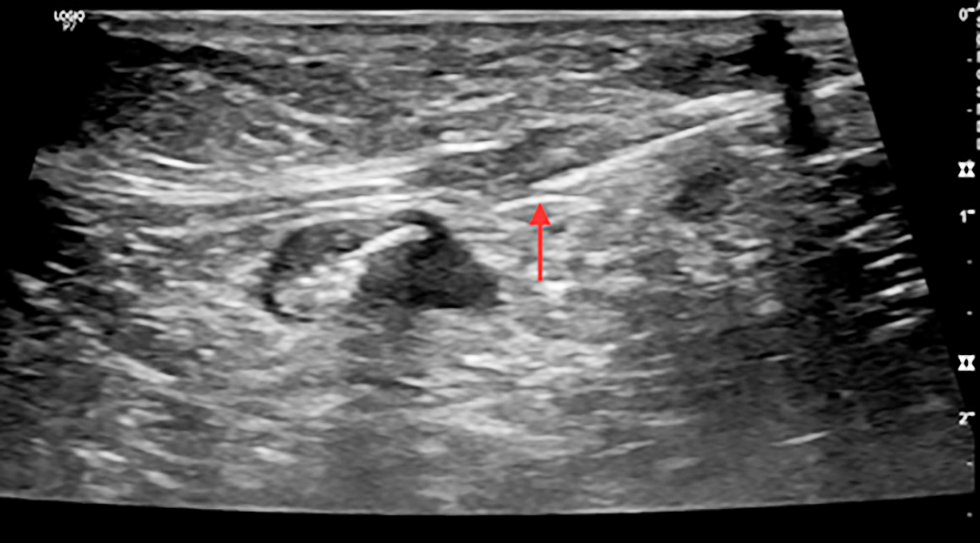

Figure 3 - Ultrasound image showing clip insertion with needle in a pathological axillary lymph node (cN1) in a female with early breast cancer

For cN1 patients, suspicious nodes underwent US-guided clip placement pre-NAC using titanium clips. Post-NAC, patients with clipped nodes underwent wire localization before surgery under US guidance (15).

The lymph node was submitted for paraffin section assessment to reassess the frozen section results, with management modified accordingly. An example of retrieved clipped lymph node is shown in fig. 1, while clip placement procedures are illustrated in figs. 2, 3, and 4.